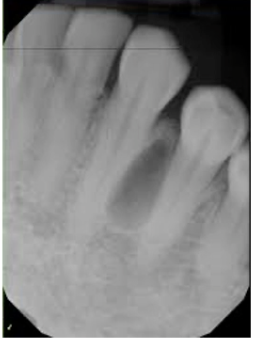

what is this?

mandible thinning on the lingual surface